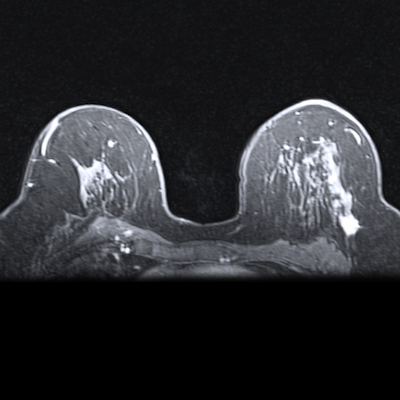

Apparent diffusion coefficient (ADC) measurements for benign and malignant BI-RADS category 4 or 5 lesions at MRI. (A, B) Benign BI-RADS category 4 lesion in a 55-year-old woman. (A) Dynamic contrast-enhanced MRI (DCE-MRI) scan shows a 12-mm, oval, circumscribed, homogeneous mass in the right posterior breast (arrow). (B) On the diffusion-weighted image, the lesion shows high diffusivity (arrow), with an ADC of 2.04 × 10-3 mm2/sec. Biopsy revealed benign fibroadenoma. (C, D) Malignant BI-RADS category 4 lesion in a 41-year-old woman. (C) DCE-MRI scan shows a 24-mm irregular, heterogeneous mass at the 3 o’clock position in the left breast (arrow). (D) On the diffusion-weighted image, the lesion demonstrates low diffusivity (arrow), with an ADC of 0.91 × 10-3 mm2/sec. Biopsy revealed invasive ductal carcinoma. All MRI scans are shown in the axial plane. (E) Box plot shows ADC measurements for 240 BI-RADS 4 and 5 lesions (63 malignant and 177 benign). Both prespecified optimal and conservative ADC cutoffs are indicated on the plot for reference: 1.53 × 10-3 mm2/sec (dashed line) and 1.68 × 10-3 mm2/sec (dotted line), respectively. All ADCs were calculated with maximum b value of 800 sec/mm2. The midline of each box shows the median value, and the box extends from first to third quartiles. The whiskers extend from the first and third quartiles to the smallest and largest values, respectively, if those values are within 1.5 times the IQR. If not, the length of the whiskers is limited to 1.5 times the IQR. Image courtesy of the RSNA.